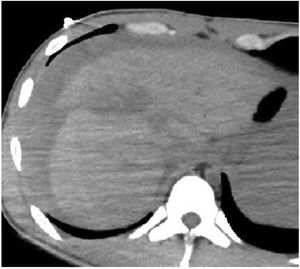

The most probable cause of death was identified in 100% of the patients, being thoracic trauma the main contributor, followed by hemorrhagic shock. Fig. 1 illustrates an example of hemorrhagic shock due to a high-grade liver injury.

The main limitation of PMCT is the identification of solid organ injuries and vascular lesions due to the absence of IV contrast and spontaneous circulation. This may cause severe injuries to go unnoticed.6,8 However, such injuries were inferred through indirect data such as the presence of significant hemoperitoneum, organ deformity, or perivascular hematoma. In addition, indirect findings of exsanguination, such as hemothorax/hemoperitoneum, or large injuries to vital organs incompatible with life, are enough to identify the cause of death without having to pinpoint the exact bleeding site. Post-mortem angiography with IV contrast would improve these results but adds complexity to the study and use of resources. Additionally, its clinical utility compared to PMCT without IV contrast is currently uncertain to date.8